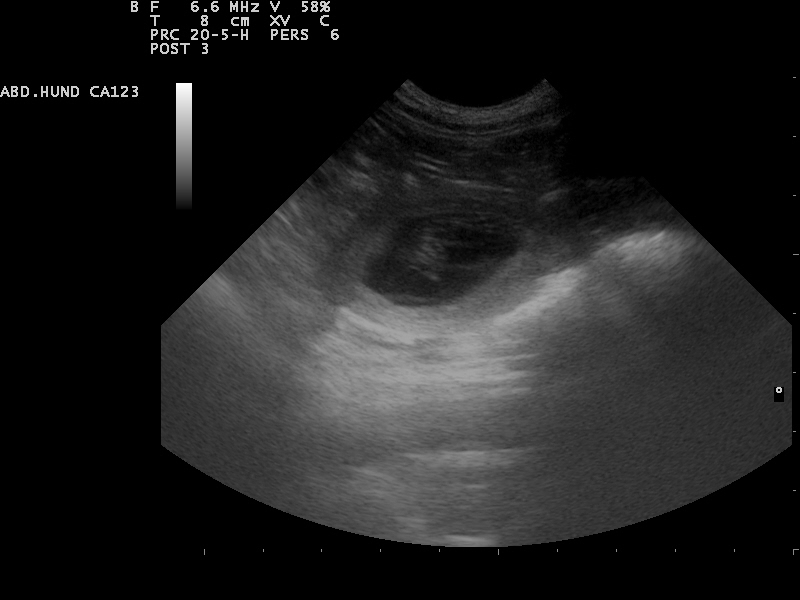

Hierfür eignet sich sehr gut die Gabe von Welpenfutter. Zu diesem Zeitpunkt kann mit einer Ultraschalluntersuchung

der Zustand der Trächtigkeit festgestellt werden. Besprechen Sie mögliche Risiken einer solchen Untersuchung mit dem Tierarzt.

Am 01.07.2014 waren wir zur Ultraschalluntersuchung und konnten

die ersten Bilder unserer Welpen bewundern.